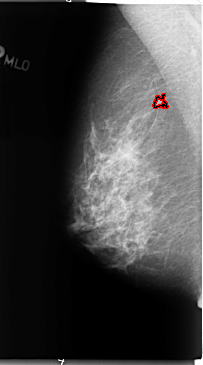

B_3096_1.LEFT_MLO

LEFT_MLO LINES 4712 PIXELS_PER_LINE 2776 BITS_PER_PIXEL 12 RESOLUTION 50 OVERLAY

FILE: B_3096_1.LEFT_MLO.OVERLAY

TOTAL_ABNORMALITIES 1

ABNORMALITY 1

LESION_TYPE MASS SHAPE IRREGULAR MARGINS ILL_DEFINED

ASSESSMENT 3

SUBTLETY 3

PATHOLOGY BENIGN

TOTAL_OUTLINES 1